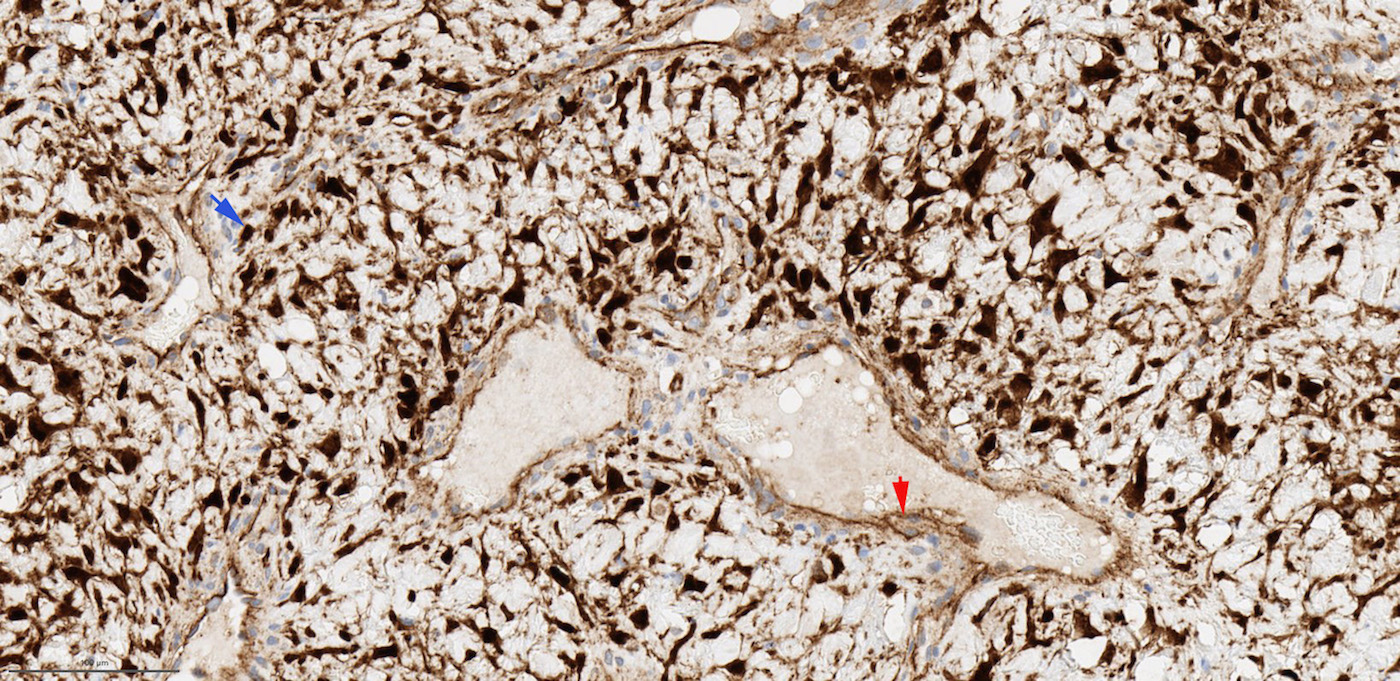

Positive stains

- SMA, HHF35 / h-caldesmon in smooth muscle wall of large vasculature (Pathology 2008;40:396, Head Neck Pathol 2018;12:52)

- CD31, CD34 and ERG highlight endothelial cells of vasculature

- AR is positive in stroma cells in 40 - 75% cases; the expression may be focal and weak (Acta Otolaryngol 2015;135:51, Am J Clin Pathol 2006;125:832, Mod Pathol 1998;11:1122)

- Beta catenin: nuclear staining in stromal cells (fibroblasts) in 70 - 90% of cases, membranous / cytoplasmic staining in endothelial cells (J Laryngol Otol 2016;130:907)

Microscopic (histologic) images

Contributed by Bin Xu, M.D., Ph.D.

Contributed by Kelly Magliocca, D.D.S., M.P.H.